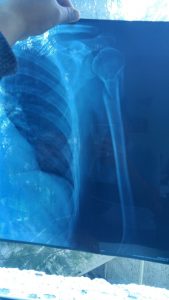

Fractura de Húmero proximal julio 17, 2017 por admin Fractura de húmero proximal, osteosíntesis con placa y tornillos.